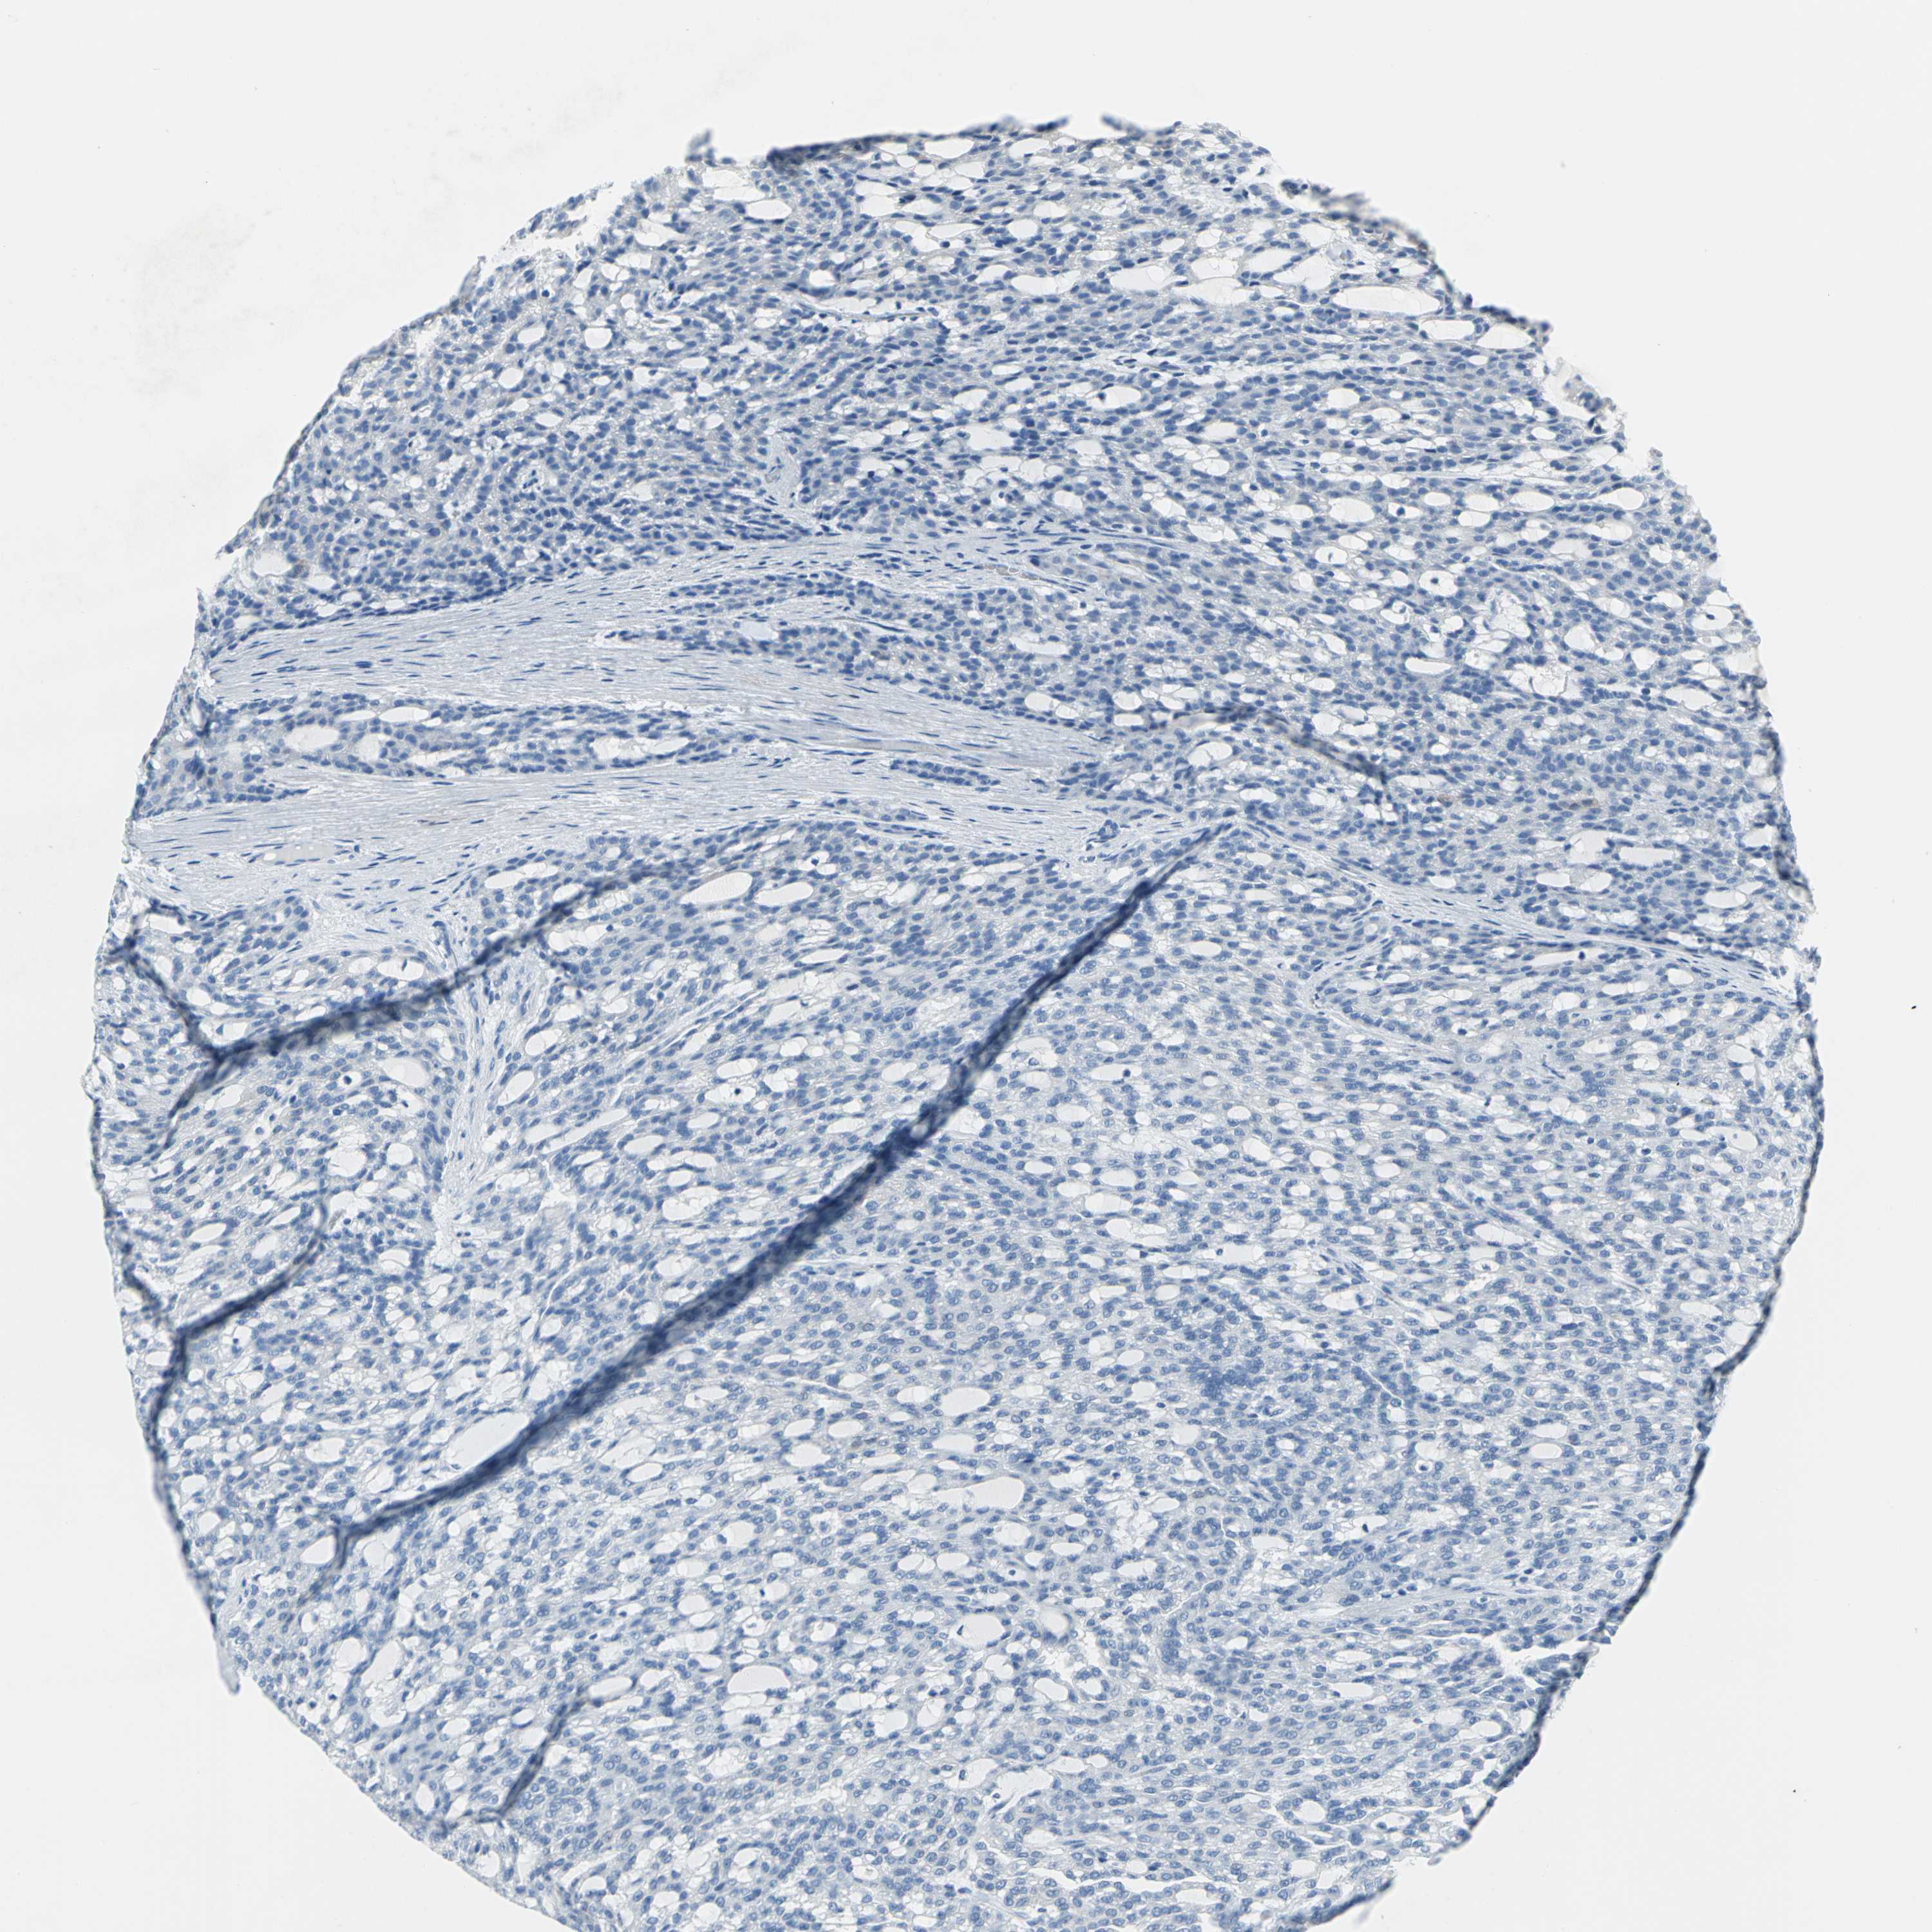

KIDNEY RENAL PAPILLARY CELL CARCINOMA (TCGA) - Interactive survival scatter ploti

The Survival Scatter plot shows the clinical status (i.e. dead or alive) for all individuals in the patient cohort, based on the same data that underlies the corresponding Kaplan-Meier plots. Patients that are alive at last time for follow-up are shown in blue and patients who have died during the study are shown in red.

The x-axis shows the expression levels (FPKM) of the investigated gene in the tumor tissue at the time of diagnosis. The y-axis shows the follow-up time after diagnosis (years). Both axes are complimented with kernel density curves demonstrating the data density over the axes. The top density plot shows the expression levels (FPKM) distribution among dead (red) and alive patients (blue). The right density plot shows the data density of the survived years of dead patients with high and low expression levels respectively, stratified using the cutoff indicated by the vertical dashed line through the Survival Scatter plot. This cutoff is automatically defined based on the FPKM cutoff that minimizes the p-score. The cutoff can be changed by dragging the vertical line or by entering a cutoff value in the square labeled "Current cut-off".

Under the Survival Scatter plot the p-score landscape (black curve; left axis) is shown together with dead median separation (red curve; right axis). Dead median separation is the difference in median mRNA expression between patients who have died with high and low expression, respectively. It is calculated as follows: median FPKM expression of dead patients with high expression - median FPKM expression of dead patients with low expression. This is intended to aid the user in visually exploring custom cutoffs and the associated p-scores and dead median separation.

Individual patient data is displayed and can be filtered by clicking on one or more of the category buttons on the top of the page. Categories describing expression level and patient information include: high, low, alive, dead, female, male and tumor stages. The scale of the x-axis can be toggled between linear and log-scale by clicking on the "x log" button. Mouse-over function shows TCGA ID, patient information and mRNA expression (FPKM) for each patient.

& Survival analysisi

Kaplan-Meier plots summarize results from analysis of correlation between mRNA expression level and patient survival. Patients were divided based on level of expression into one of the two groups "low" (under cut off) or "high" (over cut off). X-axis shows time for survival (years) and y-axis shows the probability of survival, where 1.0 corresponds to 100 percent.

SFN is not prognostic in Kidney Renal Papillary Cell Carcinoma (TCGA)

Best expression cut offi

Based on the FPKM value of each gene, patients were classified into two groups and association between prognosis (survival) and gene expression (FPKM) was examined. The best expression cut-off refers the FPKM value that yields maximal difference with regard to survival between the two groups at the lowest log-rank P-value. Best expression cut-off was selected based on survival analysis .

When clicking on this number, the vertical dashed line indicating cut-off, the interactive survival plot, and the Kaplan-Meier curve will be adjusted to show results based on the best expression cut-off.

: 95.38